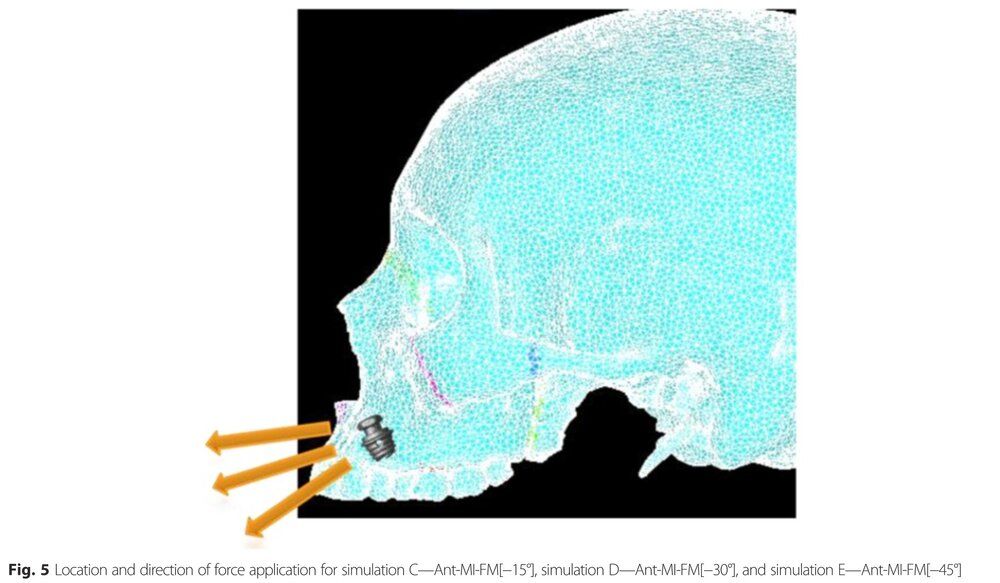

From this paper this is the typical maxilla displacement resulting from a microimplant assisted palate expander like MSE, Hyrax using a facepuller at a -30 degrees angle:

Look at how insignifiant is the forward displacement and how it displace your maxilla downward.

Now look at the displacement if the micro-implant was placed in a better location with a pulling angle of -15 degrees (Simulation C, picture on the right on the second picture) :

look at how signifiant is the forward displacement, look at how the maxilla rotate ccw.

From this paper this is the typical maxilla displacement resulting from a microimplant assisted palate expander like MSE, Hyrax using a facepuller at a -30 degrees angle:

Look at how insignifiant is the forward displacement and how it displace your maxilla downward.

Now look at the displacement if the micro-implant was placed in a better location with a pulling angle of -15 degrees (Simulation C, picture on the right on the second picture) :

look at how signifiant is the forward displacement, look at how the maxilla rotate ccw.